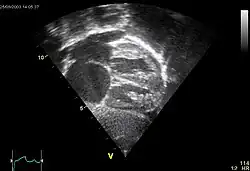

Le diagnostic est fait par échocardiographie doppler devant les signes cliniques décrits. L'examen peut montrer directement un trou (appelé solution de continuité) dans le septum inter auriculaire, et permet d'apprécier la localisation et l'importance de celui-ci, mesuré par le calcul du rapport entre le débit systémique et du cœur droit. Le doppler permet de visualiser le shunt et de mesurer la différence de pression entre les deux oreillettes par la mesure de la vitesse du flux.

Le recours à l'échographie transœsophagienne pour visualiser la communication est systématique chez l'adulte si une fermeture est envisagée, afin de préciser l'anatomie des lésions et de mesurer les berges qui permet de connaître la possibilité d'un traitement percutané.

L'échographie permet d'apprécier le retentissement de la communication au niveau des cavitès droites par la recherche d'une dilatation de ces cavitès et l'évaluation des pressions droites ainsi que la fonction du ventricule droit.